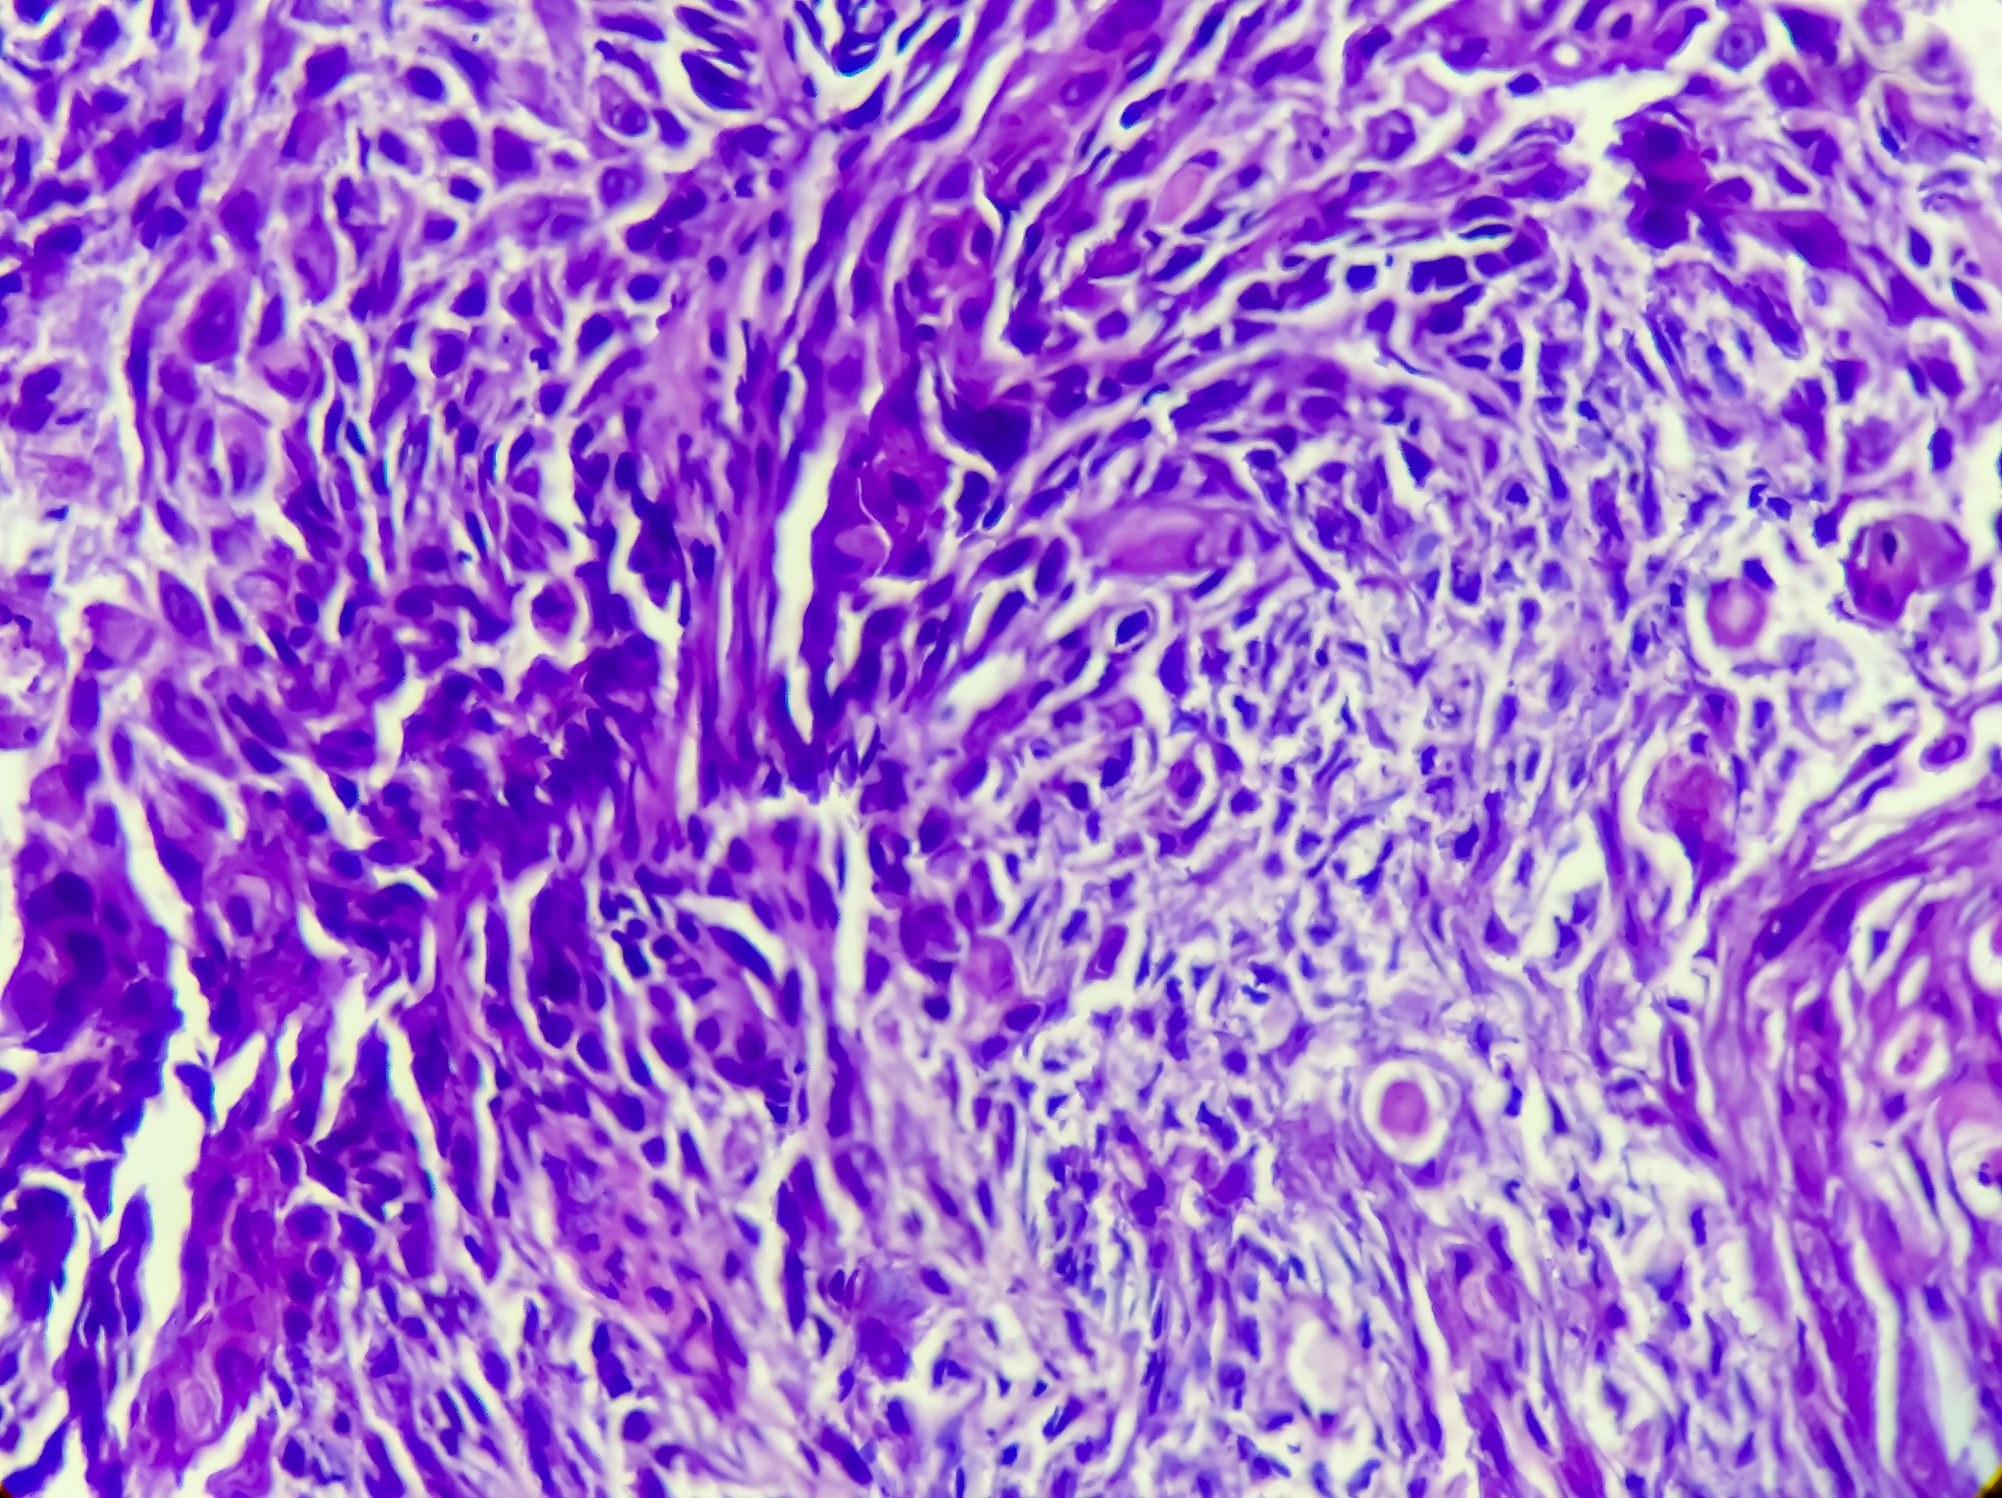

• Métastases cutanées et en particulier faciales

Manifestations rares du cancer de l’œsophage

• Cases

• Chirurgie

• Dermatologie et vénérologie

• Formation continue

• Gastro-entérologie et hépatologie

• Oncologie

• RX